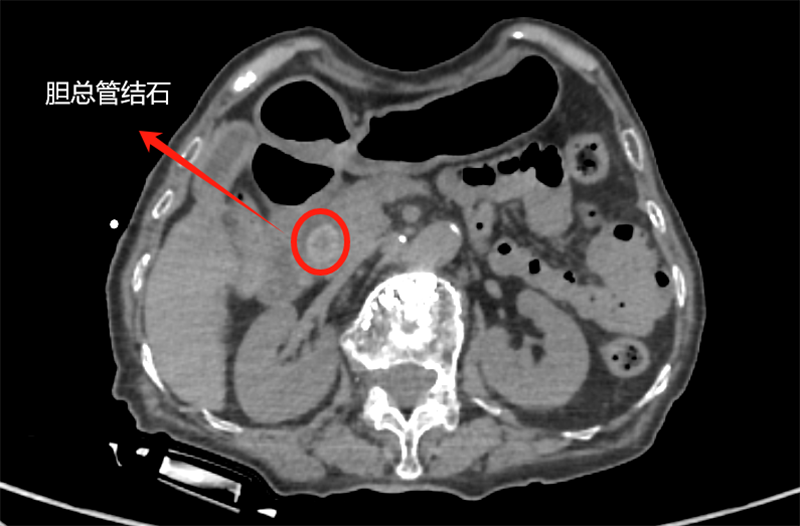

看著老人的狀態(tài)越來越差,家屬急得團團轉(zhuǎn),輾轉(zhuǎn)來到普外科。王龍華主任接診后,未沿用“腫瘤”初診,而是重新為張大娘完善了各項檢查,并聯(lián)合智慧影像中心專家團隊開展多學(xué)科討論,反復(fù)核對影像細(xì)節(jié)、分析病情。當(dāng)“不是腫瘤,是膽總管結(jié)石”的結(jié)論出來時,家屬懸了好幾天的心終于落了地,激動地說:“幸好沒放棄!”

手術(shù)當(dāng)天,術(shù)中造影顯示,張大娘膽總管下段的結(jié)石實際尺寸比術(shù)前評估更大,手術(shù)難度增加。面對挑戰(zhàn),劉主任不斷調(diào)整策略:嘗試多種取石工具,反復(fù)用擴張球囊擴張膽總管壺腹部,最終借助取石球囊成功將結(jié)石推入腸道,手術(shù)全程順利。